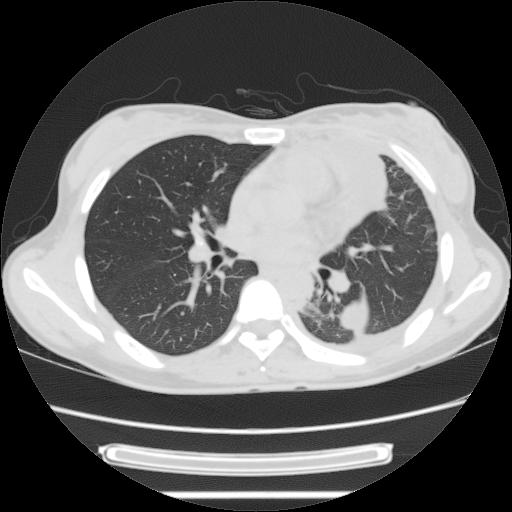

标题: CT21561:外院胸片提示胸腔积液,行CT检查。 [打印本页]

女,29岁,胸部不适,在外院胸片提示胸腔积液,到我院ct检查。

肺窗:

1、左侧包裹性积液伴叶间积液 2、右肺多发结节考虑增殖结节

左侧纵隔胸膜包裹性积液、左侧胸腔积液、胸膜肥厚粘莲,考虑结核性胸膜炎

左肺上叶不张,左侧胸水,叶间裂积液,纵隔淋巴结,脾脏钙化,考虑左肺上叶支气管内膜结核,结核性胸膜炎,脾结核

考虑:1.两肺tb;2.左侧胸膜炎、胸腔积液。

考虑两肺结核,左侧包裹性积液,叶间积液。

支持两肺继发性肺结核,左侧胸膜腔包裹性积液、胸膜肥厚,脾内多发钙化(结核钙化)。

右肺多发结节。左胸腔多发包裹性积液。